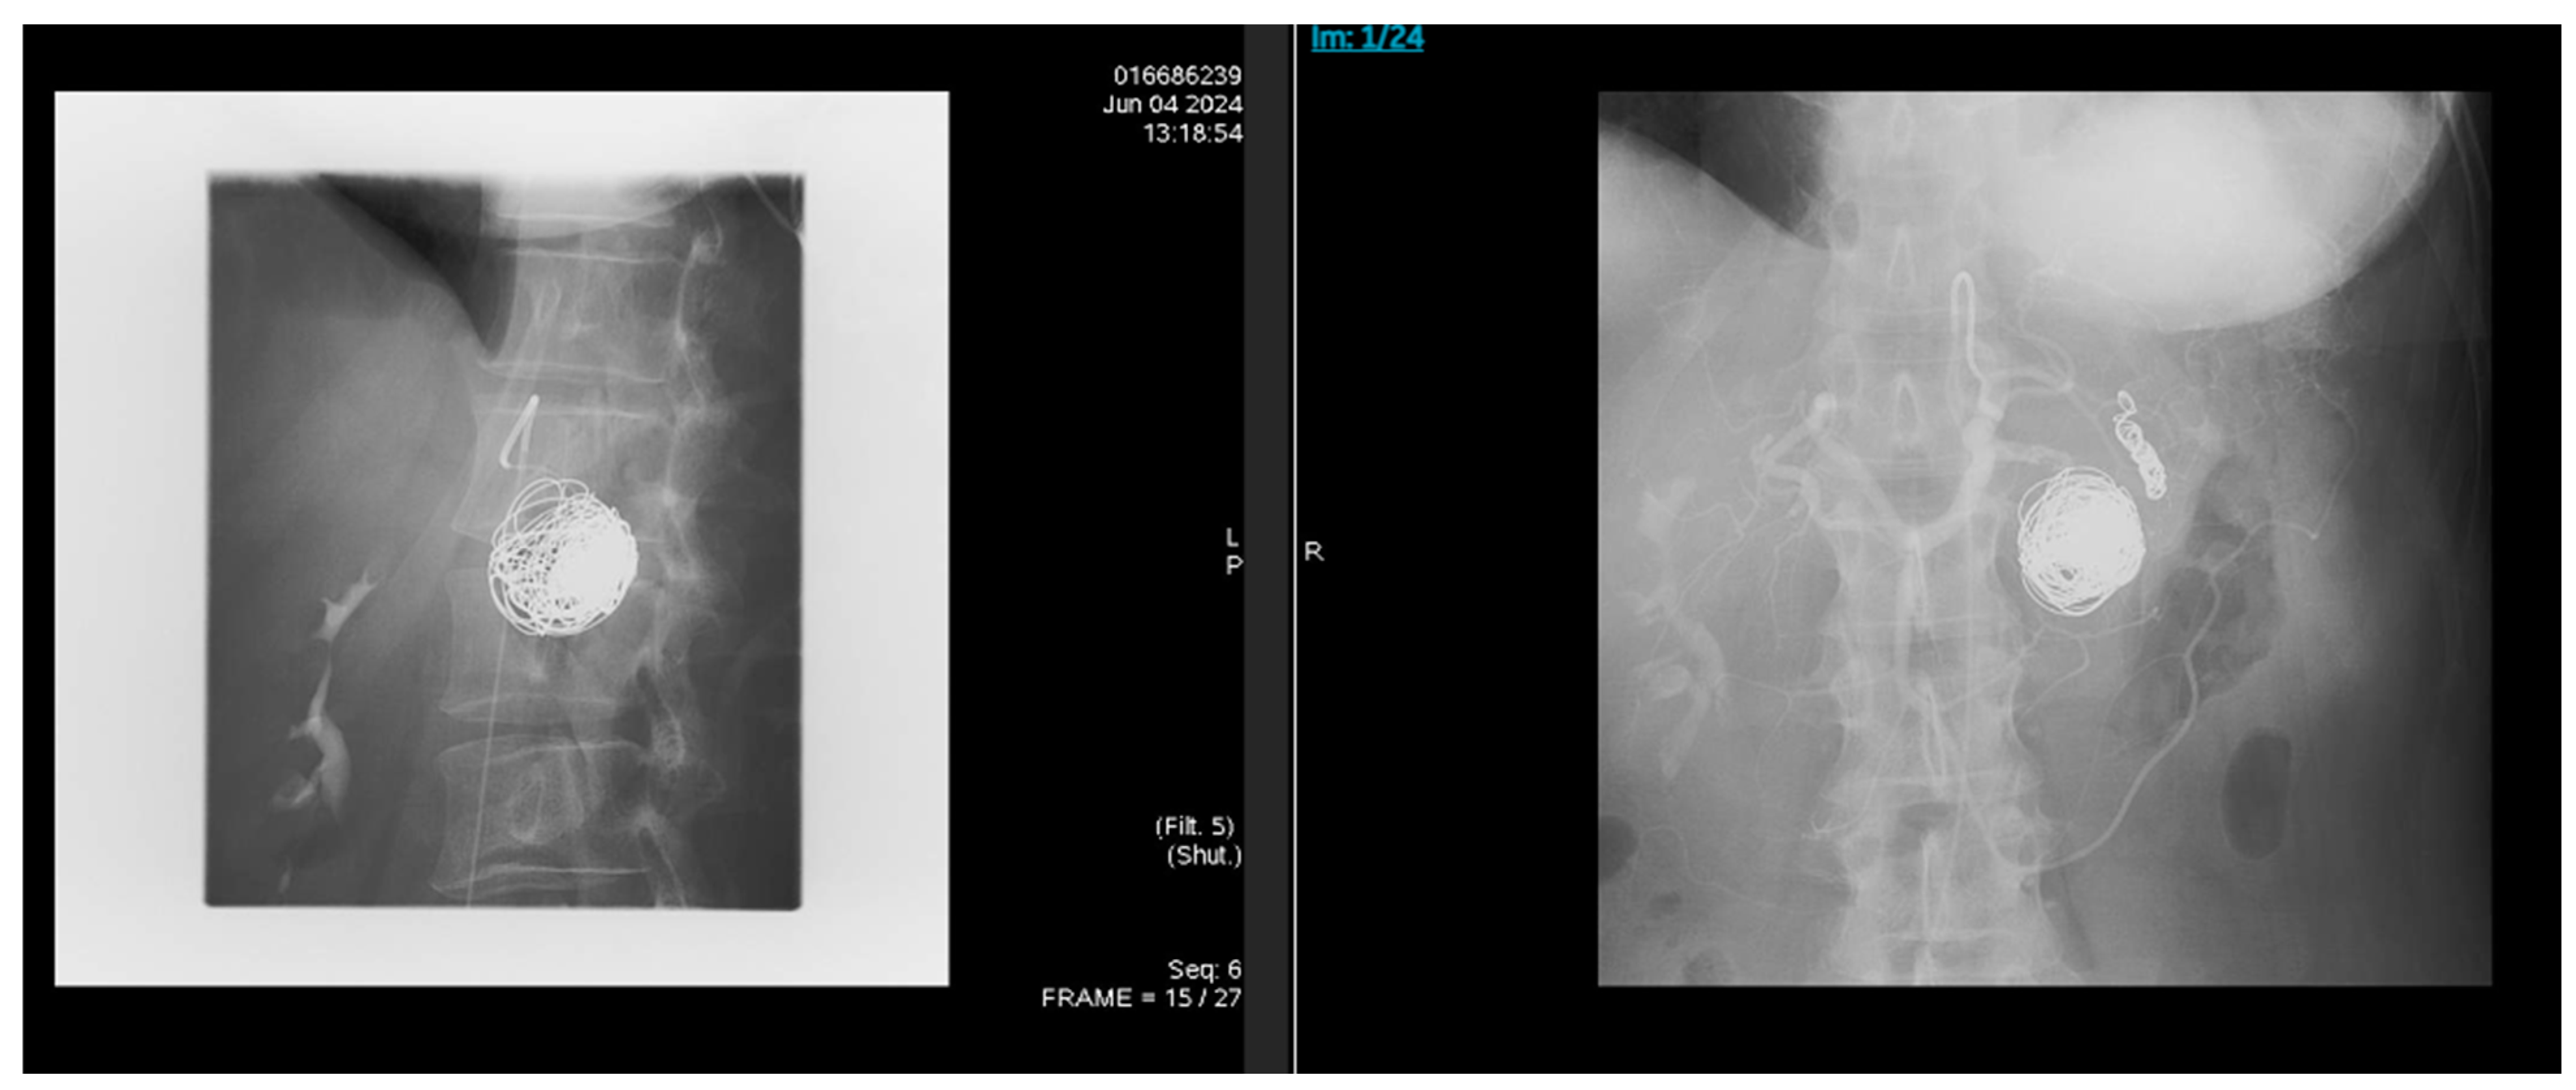

2. Case Presentation